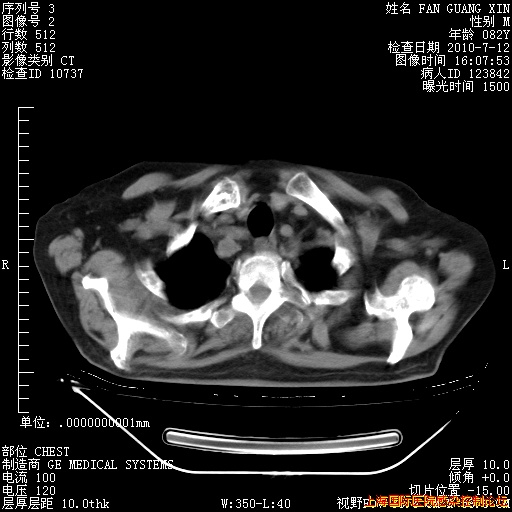

6月12日纵膈窗